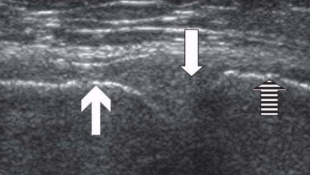

Normal US appearance of Achilles tendon

Common Achilles tendon pathology

Tendinopathy

Partial or complete tears

Retrocalcaneal bursitis

Partial or complete Achilles tendon tears